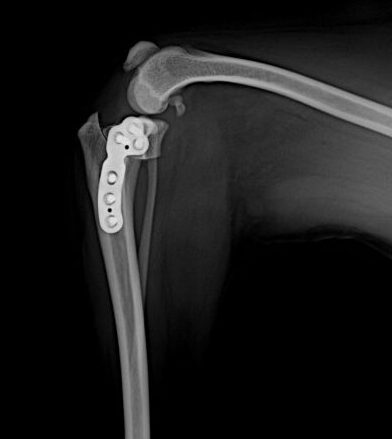

저희 병원은 응급·중환자 케어, 정형외과 수술, 건강검진,

종양·내분비 치료에 집중하는 동물병원으로

정확한 진단과 책임 있는 치료를 제공합니다.